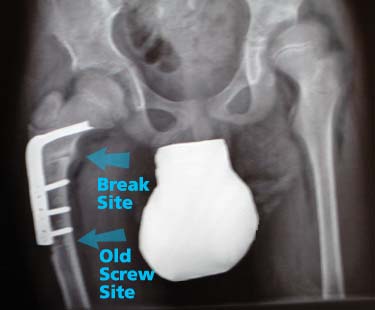

We met with Dr. Unni, and Jon’s leg has passed muster. He may now weight bear on it. For school, that means stander and walker and for home that means crawling. (Jon started his crawling last evening, and after a short distance was puffing. It’ll take him a while to get back into shape.) All of the allowed activities don’t carry any risk of major impact; anything that risks a tumble is still out for now. When the blade plate was replaced, they were able to use two of the three old screw holes. The “empty” hole has now filled in, but it’s still a stress fracture risk for a month or two.

So, after all of the good news, our attention turned to the left hip, which clearly needs to be rebuilt. Same carpentry as five years ago: (boring medical jargon) cutting the femoral head and neck and resetting it at a right angle and corrected side angle with a blade plate, and inserting a wedge of bone from the femur into a pelvic incision to improve the socket (the pelvis will fill in with bone).